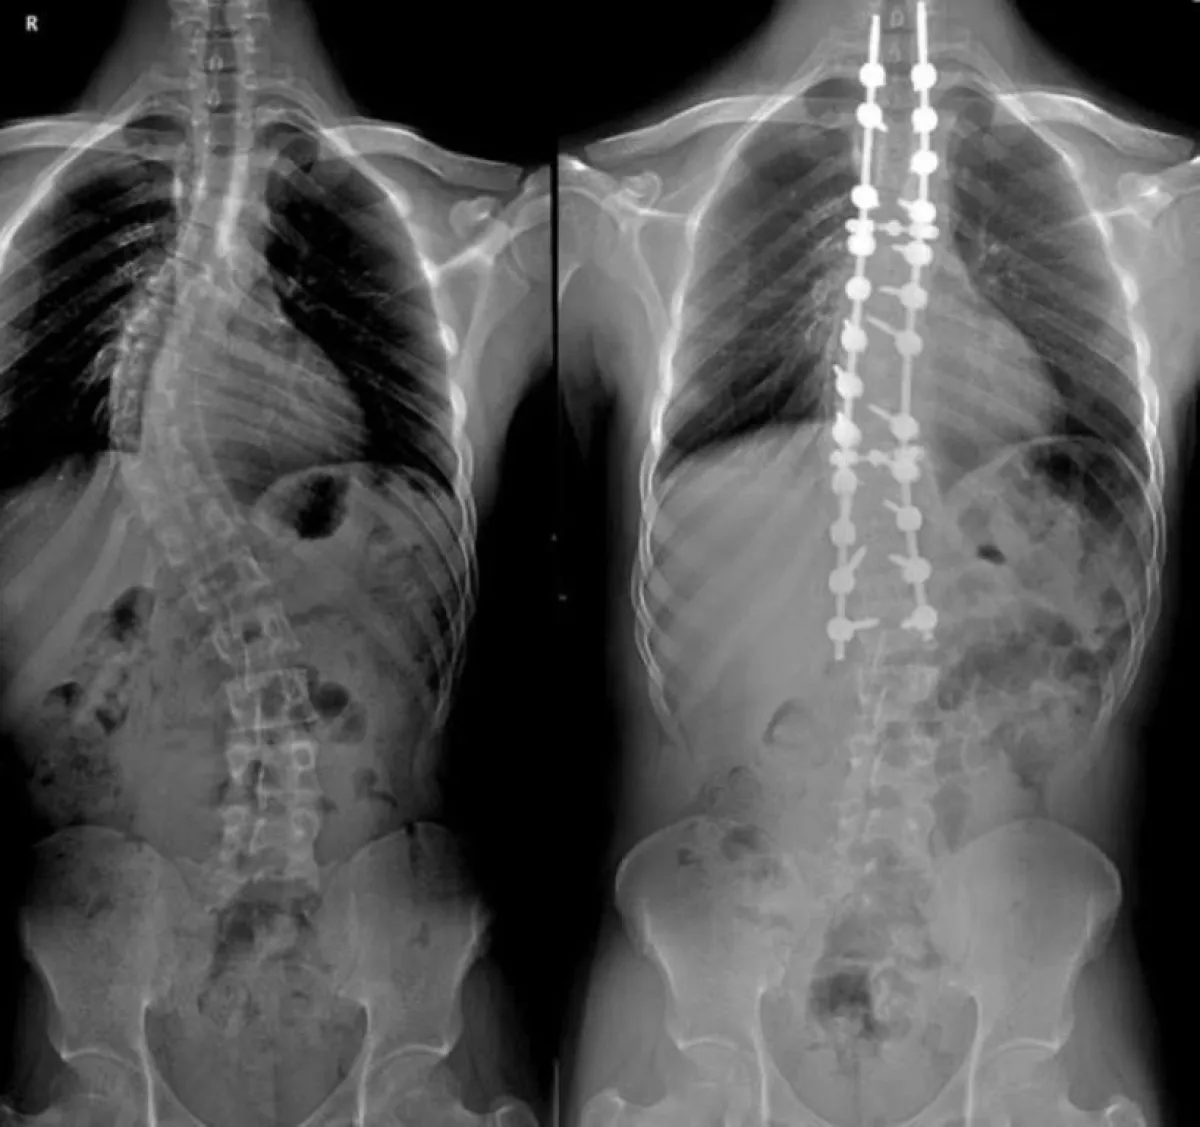

وقال: "نقوم بأداء جميع حالات الانزلاقات الغضروفية، والخشونة في الرقبة والظهر، والانزلاقات الفقارية البسيطة والمعقدة، والجنف في المستشفى بأحدث التقنيات وبأقل نسبة من المضاعفات".